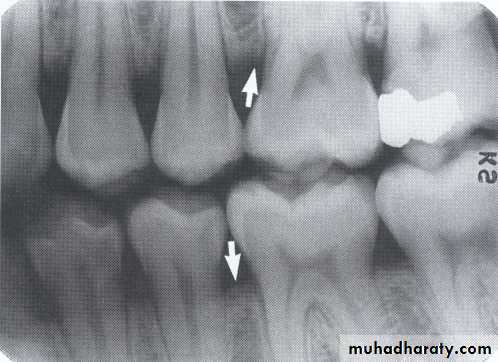

1. Horizontal bone loss:- When loss occurs on a plane that is parallel with a line drown.

2.Vertical bone loss:- when there is greater bone loss in one tooth than on the adjacent tooth, so the bone level is not parallel with a line joining the CEJ.